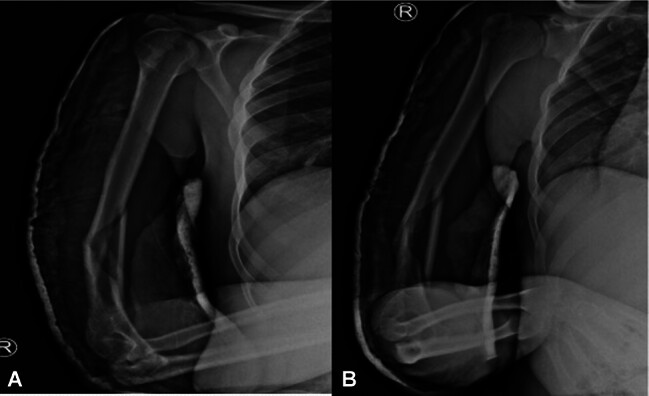

Abstract Image